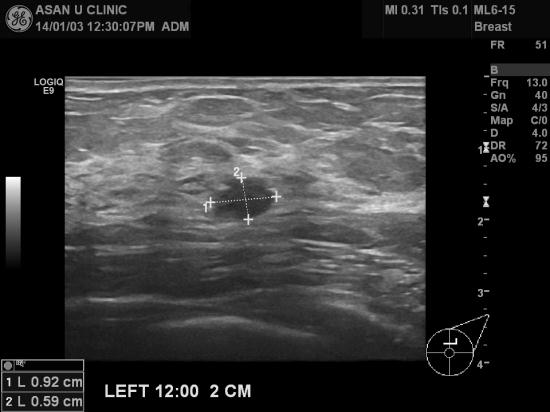

건강검진의 유방암검진에서 이상소견있어

조직검사위해 본원에 의뢰되신 60세 여성입니다.

좌측유방에는 0.8cm전후의 결절이 있으나

좌측 액와부에 1.5cm이상으로 비후된 두개의 림프절이 있습니다.